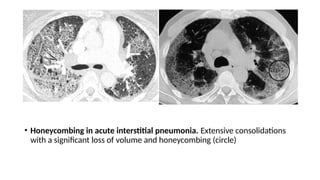

• Honeycombing in acute interstitial pneumonia. Extensive consolidations

with a significant loss of volume and honeycombing (circle)

• Honeycombing inacute interstitial pneumonia. Extensive consolidations with a significant loss of volume and honeycombing (circle)